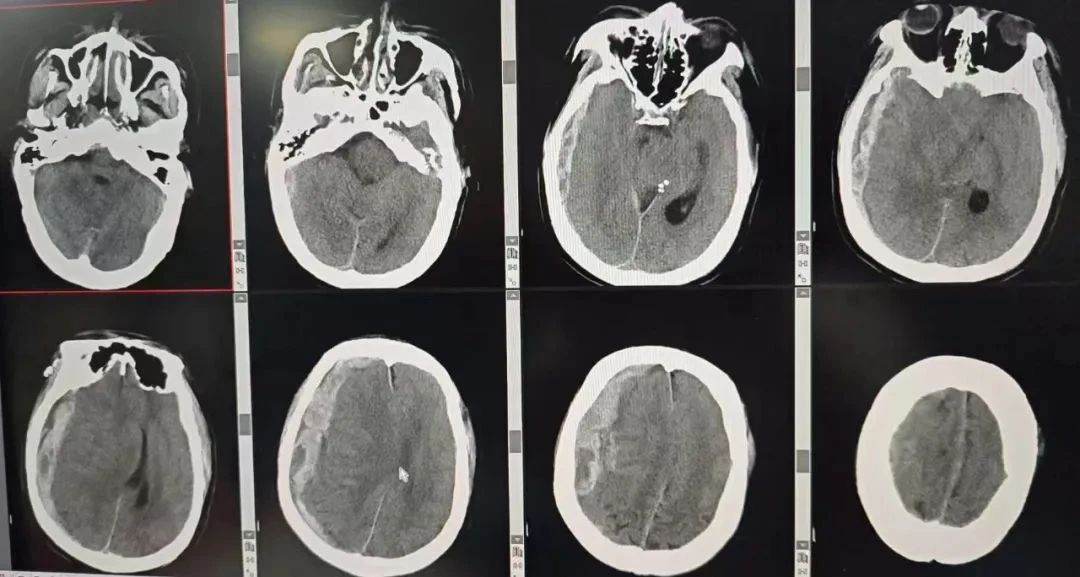

术后,患者转入神经外科重症监护室,医护团队24小时监测生命体征,动态调整治疗方案。5月2日上午复查CT显示颅内血肿完全清除,颅内压稳定,双侧瞳孔较术前明显缩小,意识状态逐步改善。“手术降压成功,救治有效!”神经外科主任李松年表示,患者已度过最危险阶段,后续将重点预防并发症、促进神经功能康复。同时,池超超副主任介绍,患者还有一正在读大一的女儿,患者可以说是家庭的顶梁柱,且经了解,其家庭经济情况并不宽裕。一开始,家属背负着经济和思想的双重负担,但秉着救死扶伤的医者使命,参与救治的专家们不断安抚家属、介绍手术的可行性,同时也与交警部门一起解释了车祸抢救的相关政府补助措施,打消了家属的顾虑,最终成功手术。

手术后CT